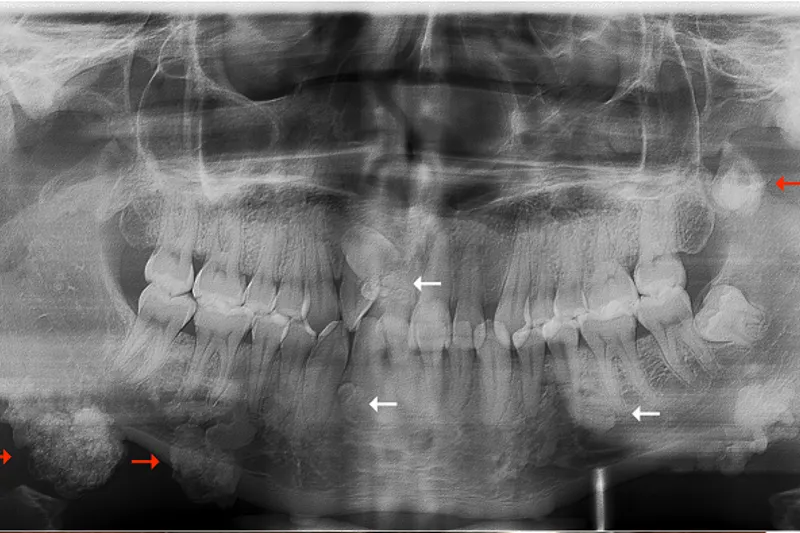

BAGGRUND – Familiær adenomatøs polypose er en sjældent forekommende arvelig tarmsygdom, som er karakteriseret ved udvikling af fra 100 til flere tusinde kolorektale polypper og ekstrakoloniske manifestationer, herunder osteomer i kæberne og tandanomalier.

PATIENTTILFÆLDE – En 29-årig mand blev henvist fra sin privatpraktiserende læge til Kæbekirurgisk Afdeling, Aalborg Universitetshospital, med henblik på diagnostik og behandling af let symptomgivende og kosmetisk skæmmende langsomt voksende hårde hævelser bilateralt langs basis mandibulae.

Patienten var kendt med familiær adenomatøs polypose.

Histologisk undersøgelse af excisionsbiopsier viste forandringer forenelige med osteomer som led i familiær adenomatøs polypose.

Familiær adenomatøs polypose er en sjælden arvelig sygdom forårsaget af en gendefekt. Mutationen giver anledning til udvikling af kolorektale adenomer og forekomst af ekstrakoloniske manifestationer, heriblandt osteomer i kæberne og dentoalveolære forandringer. Osteomer i kæberne tillægges en prædiktiv værdi, fordi de ofte kan påvises hos børn og unge inden udviklingen af kolorektale adenomer. Ubehandlet udvikler alle patienter kolorektal cancer; derfor er kendskab til de kliniske og radiologiske afvigelser essentielt for at iværksætte tidlig diagnostik og behandling.